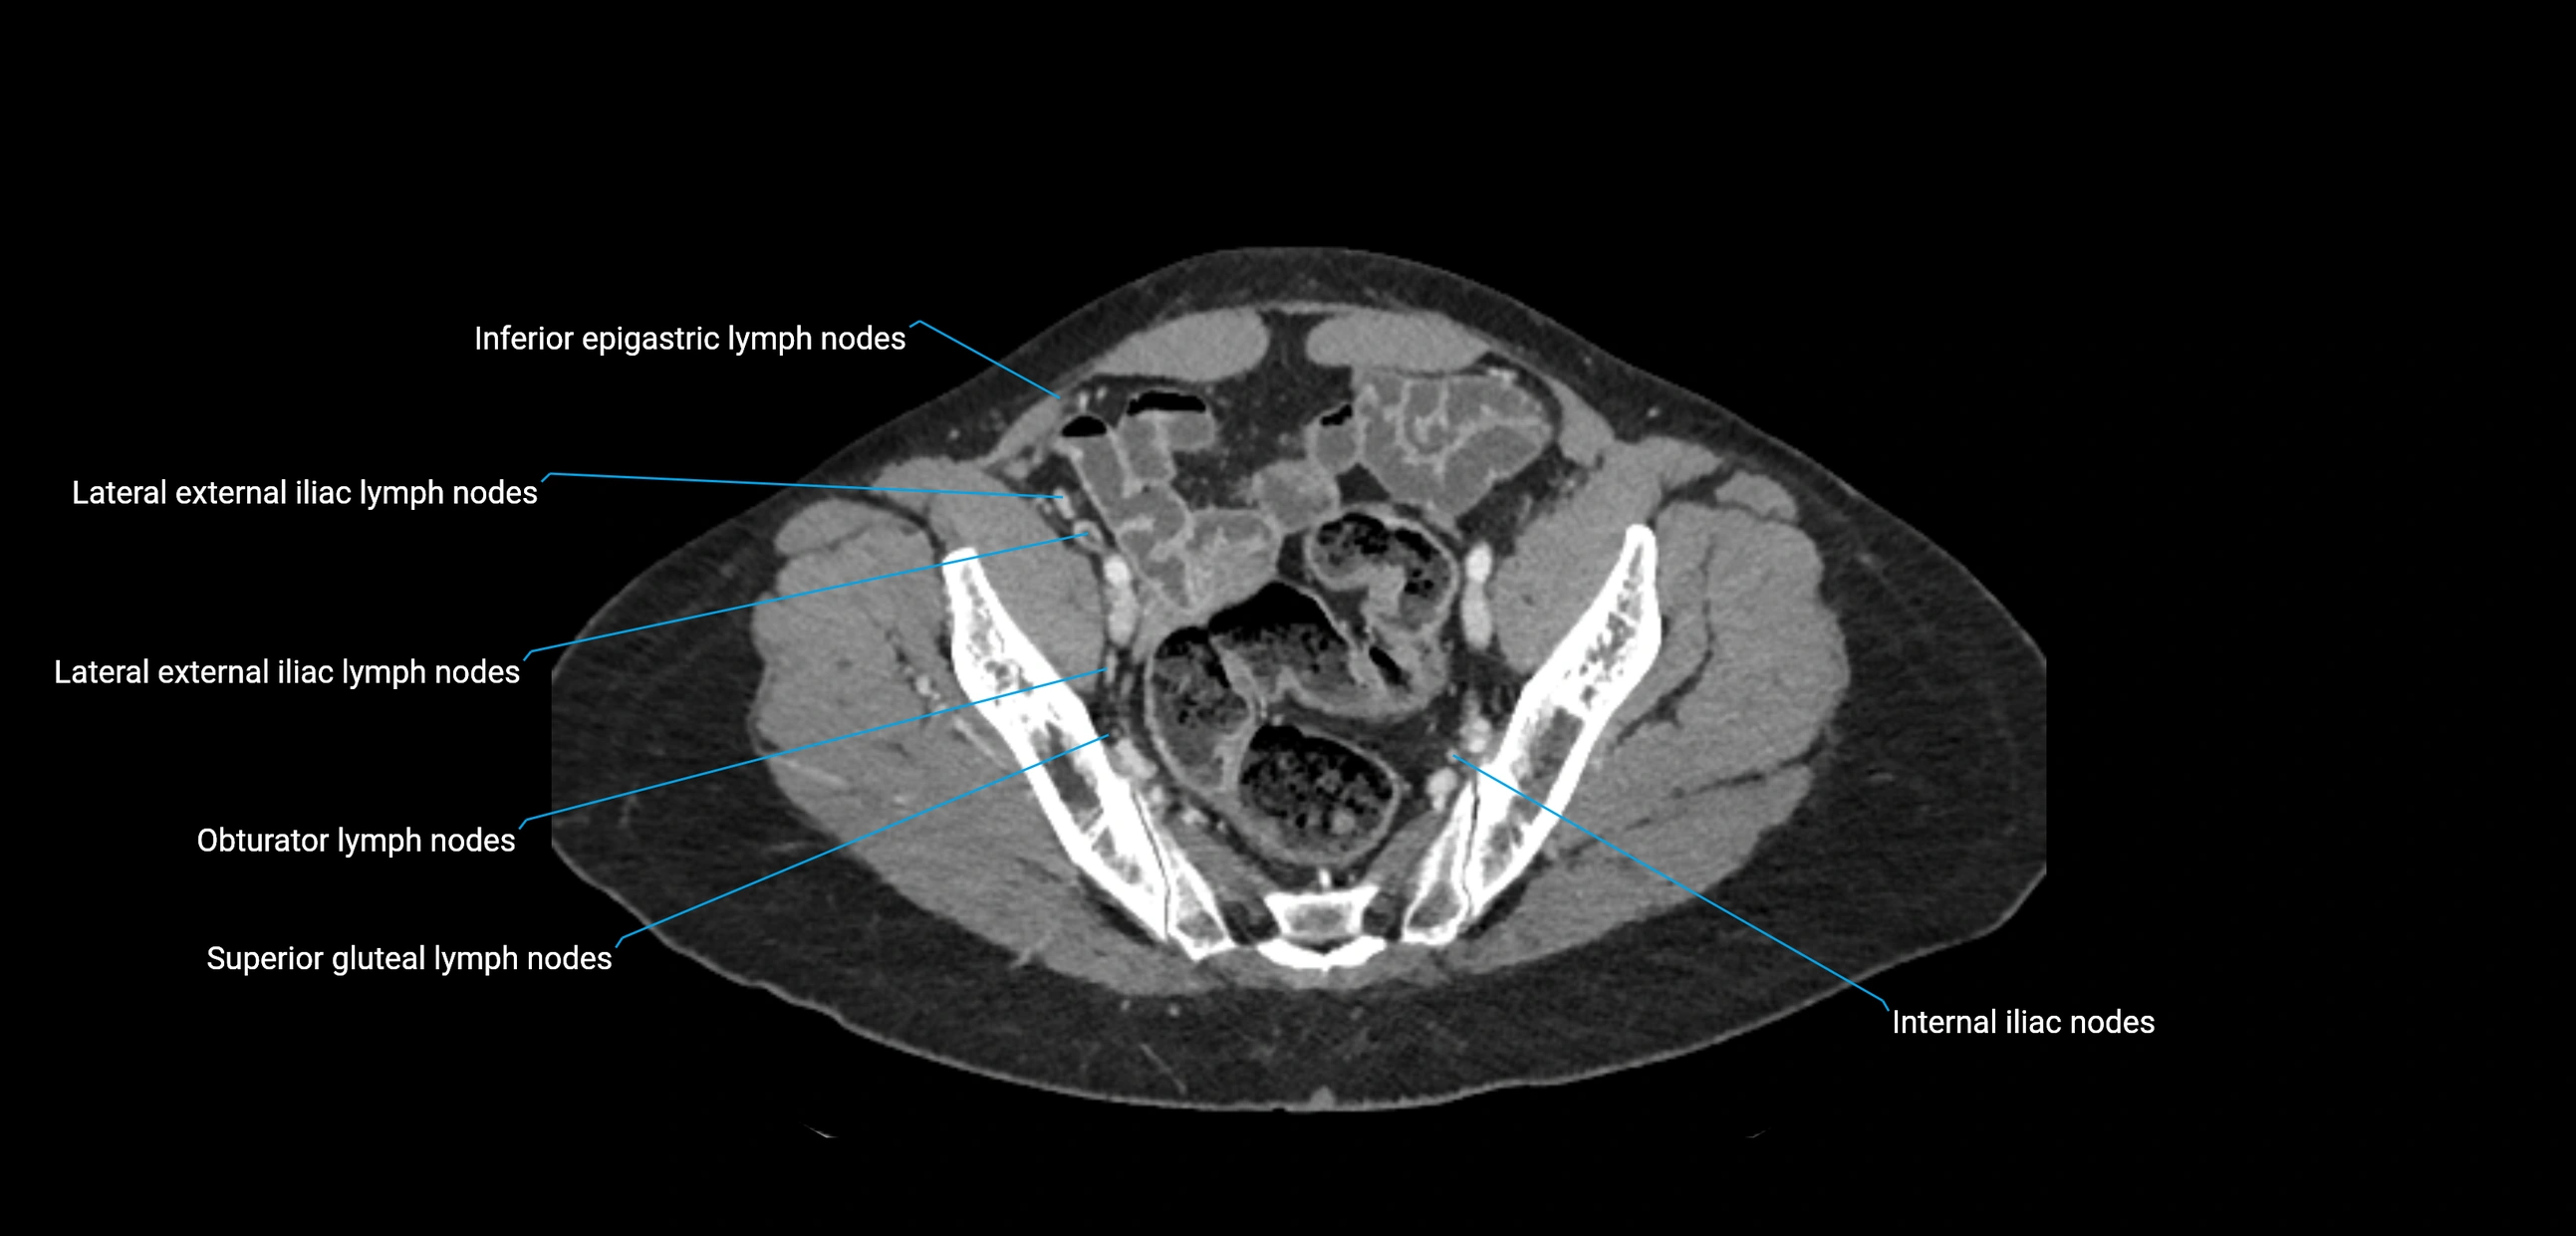

CT Appearance

CT Pre-Contrast:

• Nodes appear as soft-tissue density nodules adjacent to the aorta and IVC

• Calcification may be seen in chronic infections (e.g., tuberculosis)

CT Post-Contrast:

• Normal nodes enhance homogeneously

• Malignant nodes may show heterogeneous enhancement, central necrosis, or conglomerate formation

• Size >1 cm short axis is suspicious, though morphology and distribution are equally important

CT Venography (CTV):

• Demonstrates nodal encasement or compression of adjacent vessels (aorta, IVC, renal veins)

• Useful in staging testicular and ovarian malignancies

• Provides 3D reconstructions for retroperitoneal lymph node dissection planning